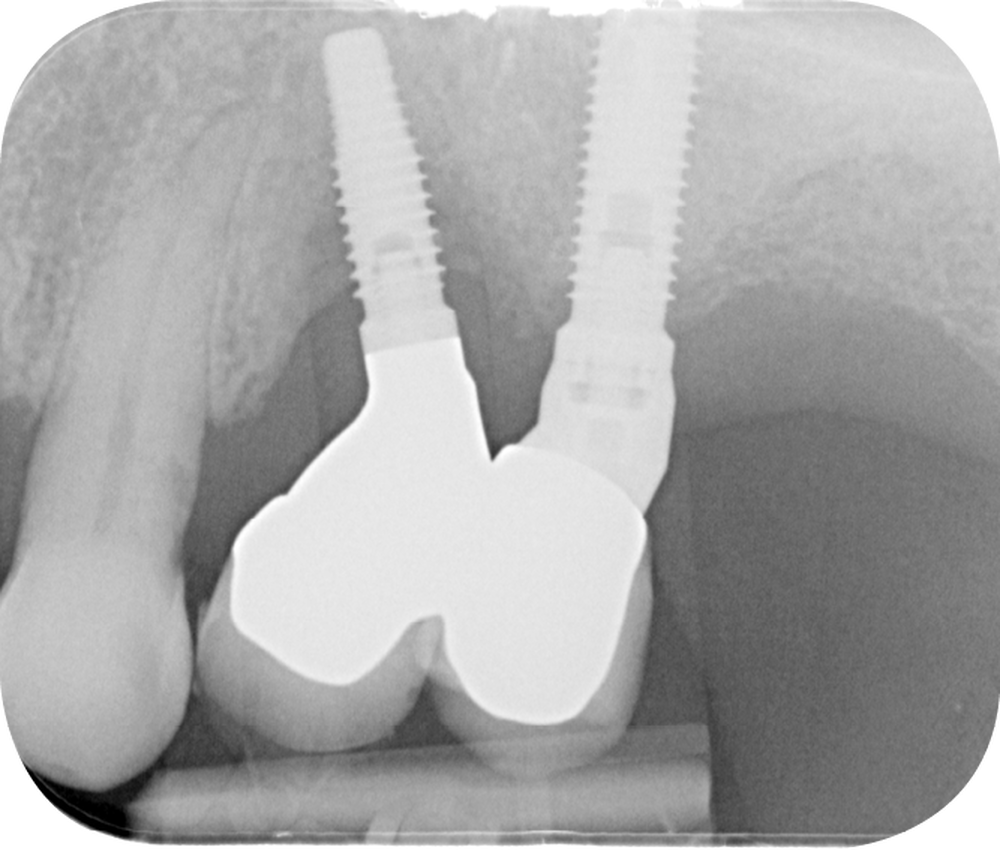

Au niveau d’un implant atteint de péri-implantite, la densité la plus importante de bactéries se trouve au niveau de la jonction pilier-implant [5]. La colonisation bactérienne de cette connectique se fait lors des manipulations…